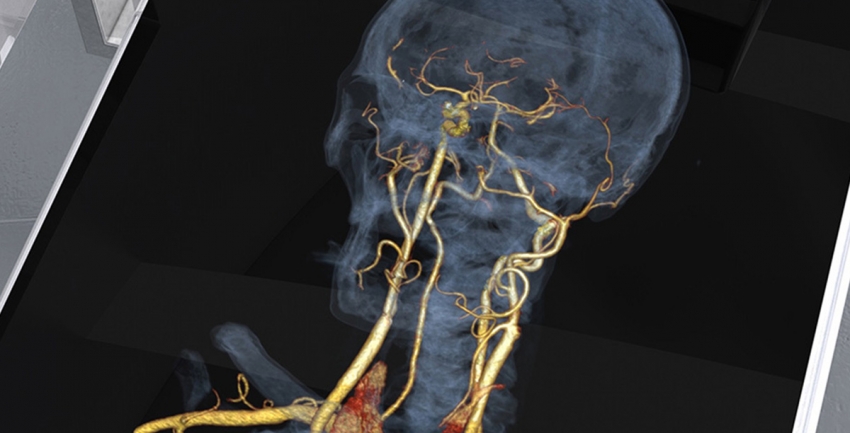

Carotid Stenting

Carotid angioplasty and stenting is a minimally invasive procedure performed after a diagnostic angiogram to confirm the degree of vessel narrowing. During angioplasty, a balloon catheter is guided to the area of the blockage or narrowing. When the balloon is inflated, blood flow improves. A carotid stent (a small, metal mesh tube) is placed inside the carotid artery at the site of the blockage and provides support to keep the artery open.

Arteriovenous Malformation (AVM) and Arteriovenous Fistula (AVF) Embolizations

This is a minimally invasive treatment for vessel malformations and fistulas that occur in the brain. A catheter is inserted through the skin into an artery and, using image-guidance, is maneuvered through the body to the target, where it is used to deliver a liquid similar to glue that clogs up the abnormal connection and restores normal circulation.